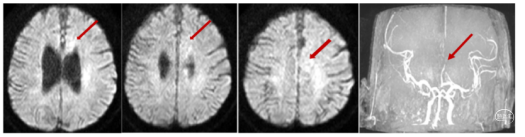

患者男,59岁,右侧肢体活动不灵1小时25分钟。神经系统:神志清楚,反应迟钝,言语基本流利,双侧额纹、鼻唇沟对称,伸舌左偏,四肢肌张力正常,右上肢肌力3级,右下肢肌力2级,右侧巴氏征(+)。NIHSS评分9分。 ASPECTS-CT评分:前循环9分。MRI显示左侧大脑前动脉区域埂塞可能,MRA大脑前动脉A2以远未显影。

初步诊断:1.急性脑梗死(左侧大脑前动脉);TOAST分型:大动脉粥样硬化型);2.高血压病3级,很高危;3. 2型糖尿病。

造影右侧大脑前动脉缺如(未发育),左侧大脑前A2段闭塞。

发病位置与病因:左侧大脑前A2段,病因考虑动脉粥样硬化,不排除ICAS可能。

治疗方案:

大脑前动脉血管较细、路径迂曲,一般抽吸导管到位比较困难,又恐4mm及以上直径的取栓支架用于大脑前动脉对血管损伤较大,遂使用3*20mm小支架联合5F 125中间导管,SWIM取栓。

手术所用耗材:取栓支架 3*20mm、远端通路导管 5F 125cm 、0.014inch 300cm微导丝、2.4F微导管、6F长鞘、0.035in泥鳅导丝、5F造影导管。

手术过程:

1、微导丝越过闭塞处到达A3段。下图1

2、5F 125中间导管辅助高到位下图2。

3、手推造影明确血栓位置下图3。

4、微导管到达A4段下图4。

5、3*20取栓支架到位回撤微导管,多点显影标记,清晰可见支架打开良好下图5。

造影显示血管再通。